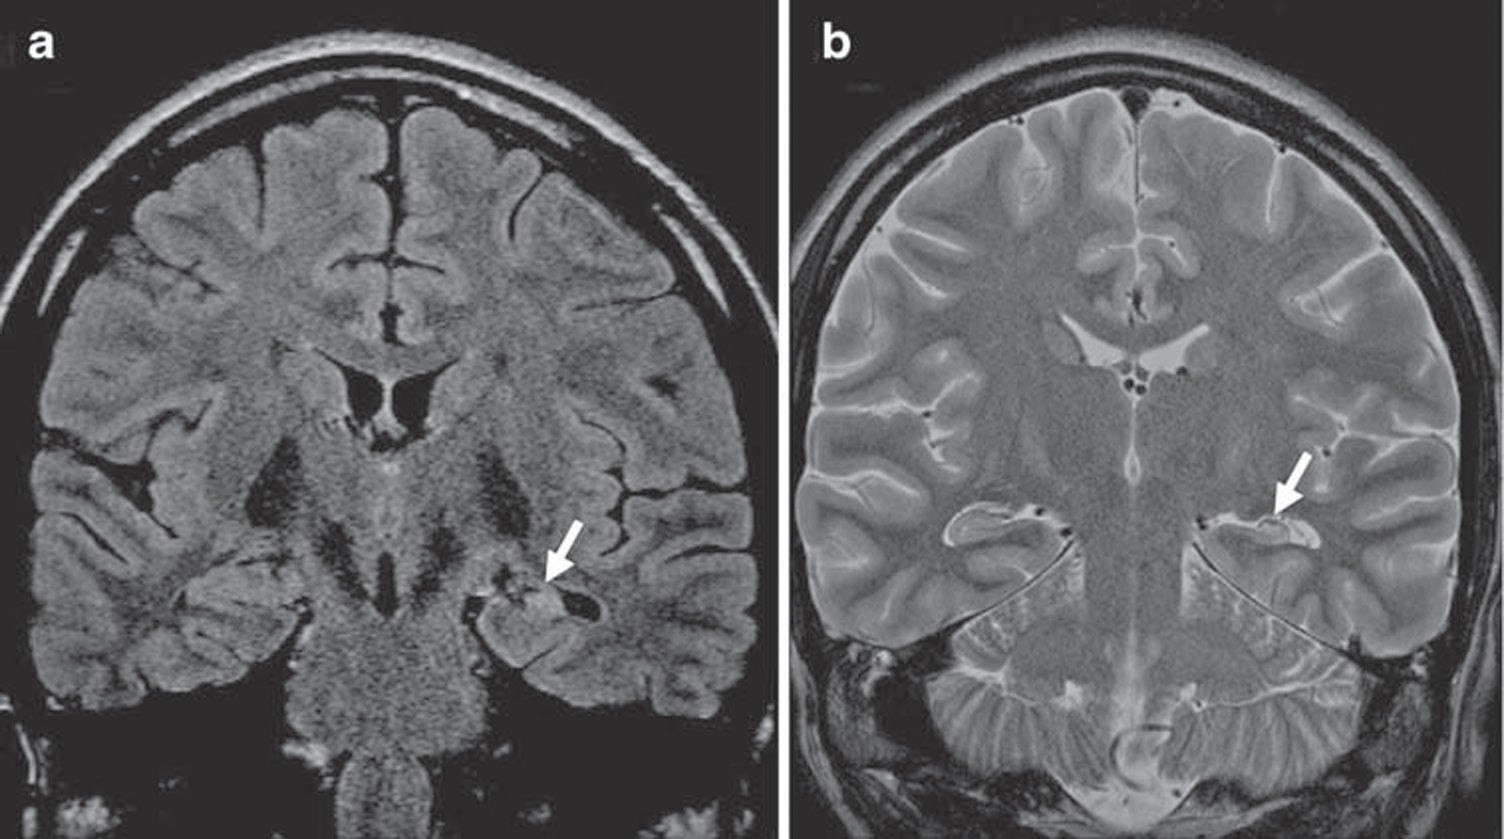

Focal cortical dysplasias fcd represent a heterogeneous group of disorders of cortical formation which may demonstrate both architectural and proliferative featuresthey are one of the most common causes of epilepsy and can be associated with hippocampal sclerosis and cortical glioneuronal neoplasms.

Klinik bildgebung und der histopathologische befund variieren erheblich sodass sich bislang noch kein international verbindliches klassifikationssystem etablieren konnte. Im folgenden werden die charakteristischen neuropathologischen befunde bei fcd und die zwei. Als fokale kortikale dysplasie abgekürzt häufig als fkd oder auch engl.

Läsionen die aus einer störung der normalen kortikalen entwicklung resultieren und umgangssprachlich häufig mit dem begriff kortikale dysplasien zusammengefasst werden sind derzeit neuroradiologisch und neuropathologisch uneinheitlich klassifiziert.